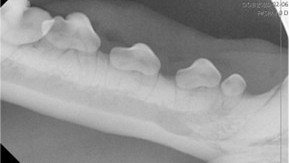

Dental Radiographs

We use advanced digital dental x-rays to gain a clear view of your pet’s oral health. This allows our team to detect hidden dental issues such as infection and design personalized treatment plans.